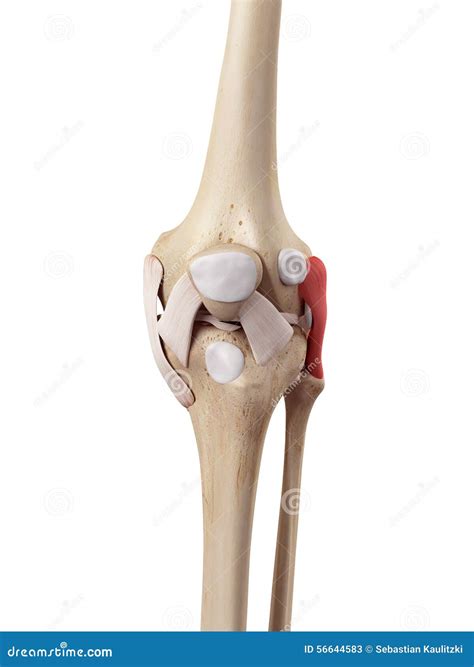

The Fibular Collateral Ligament, frequently referred to by medical professionals as the Lateral Collateral Ligament (LCL), is a critical component of the knee joint's stability. Located on the outer side of the knee, this band of fibrous connective tissue connects the femur (thigh bone) to the fibula (the smaller bone in the lower leg). While often overshadowed in popular culture by the more commonly injured Anterior Cruciate Ligament (ACL), the Fibular Collateral Ligament is essential for maintaining proper knee alignment and preventing excessive side-to-side movement, particularly when the leg is subjected to force from the inside.

Understanding the anatomy of the Fibular Collateral Ligament is crucial for grasping how it protects the knee. Unlike the Medial Collateral Ligament (MCL), which is attached to the joint capsule and the meniscus, the LCL is a distinct, cord-like structure that sits entirely outside the joint capsule. This anatomical positioning grants it a different injury profile compared to other knee ligaments.